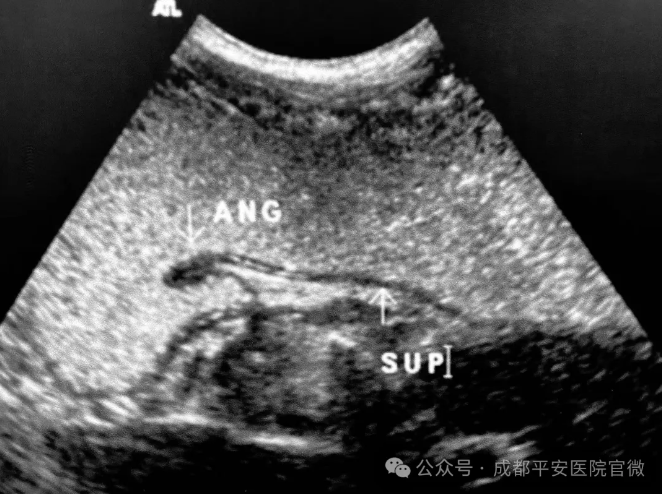

胃超声造影图像